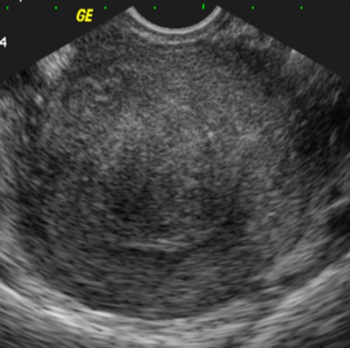

Myome sous-muqueux, arrondi, hypoéchogène

(Cliché : Dr. C. TALMANT)